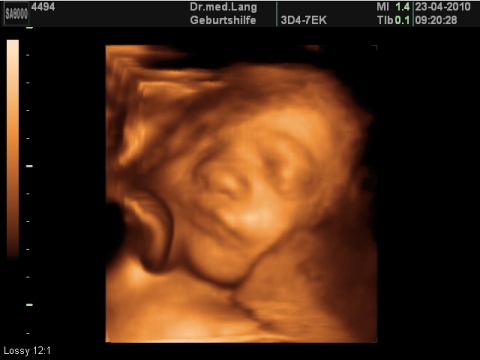

Grösse und Gewicht

Grösse: ca. 40 cm

Gewicht: 1600-1750 g

Kopfdurchmesser: 76-88 mm

Ihr Baby

Nun verschwinden auch die kleinen Falten und Runzeln, die Haut des Ungeborenen wird glatt. Pro Woche wächst es jetzt etwa einen Zentimeter. Wenn es wach ist, sind seine Augen weit geöffnet. Alle seine fünf Sinne sind entwickelt: Es kann tasten, riechen, sehen, schmecken, hören.